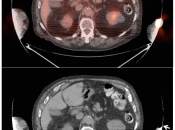

Extravasation of Injected FDG

FDG is injected intravenously. As many cancer patients have challenging venous access issues, partial extravasation of FDG during injection is not uncommon (an estimated 10% of patients have evidence of extravasation on their PET images).

Extravasation of FDG at the time of the intravenous injection can result in false positive interpretations due to:

- Focal intense uptake at the injection site.

- Linear uptake along the lymphatic channels within the arm (appearing as long vessels).

- Focal uptake in small ipsilateral axillary nodes.